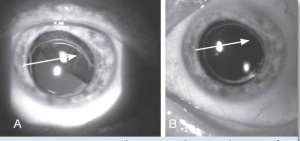

בבדיקה של החולה תתגלה מסה, לרוב מלנוטית, בענביה, שיכולה להיות ממוקמת אנטומית בחלק הקדמי של העין (בקשתית) או בחלקים האחוריים של העין (בגוף הריסני או בשכבה הדמית) (תמונה 1, תמונה 2). גידולים גדולים יכולים לערב שני אזורים אנטומיים, ולעתים אף את כל השלושה. אישוש האבחנה נעשה באמצעות בדיקת על-קול של העין הנגועה. אחוז הטעות בדיוק באבחנה של מלנומה של הענביה הוא רק 0.3% על פי ה-Collaborative Ocular Melanoma Study (COMS Study)[1].

למיקום האנטומי של הגידול יש משמעות פרוגנוסטית. מלנומה של הקשתית מהווה כ-5% מכלל המלנומות של הענביה, וגידול זה נחשב פחות אגרסיבי ביולוגית. במעקב ארוך טווח נמצא שמלנומה של הקשתית נוטה לשלוח גרורות רק ב-3% מהמקרים, ב-5% וב-10% במעקב של חמש שנים, עשר שנים ועשרים שנה בהתאמה[2]. מלנומה של הגוף הריסני היא לרוב א-תסמינית. גידול זה מהווה כ-10% מכלל המלנומות של הענביה. בשל מיקומו החבוי מאחורי הקשתית, הגילוי של המחלה נעשה בדרך כלל רק בשלבים מתקדמים. מלנומה של הגוף הריסני נחשבת לתוקפנית מבין המלנומות של הענביה. מלנומה של הדמית (Choroid) מהווה כ-85% מכלל המלנומות של הענביה. כ-50%-30% מכלל החולים עם מלנומה של הדמית ימותו תוך עשר שנים מאבחון מחלתם משנית לפיזור גרורתי[3].